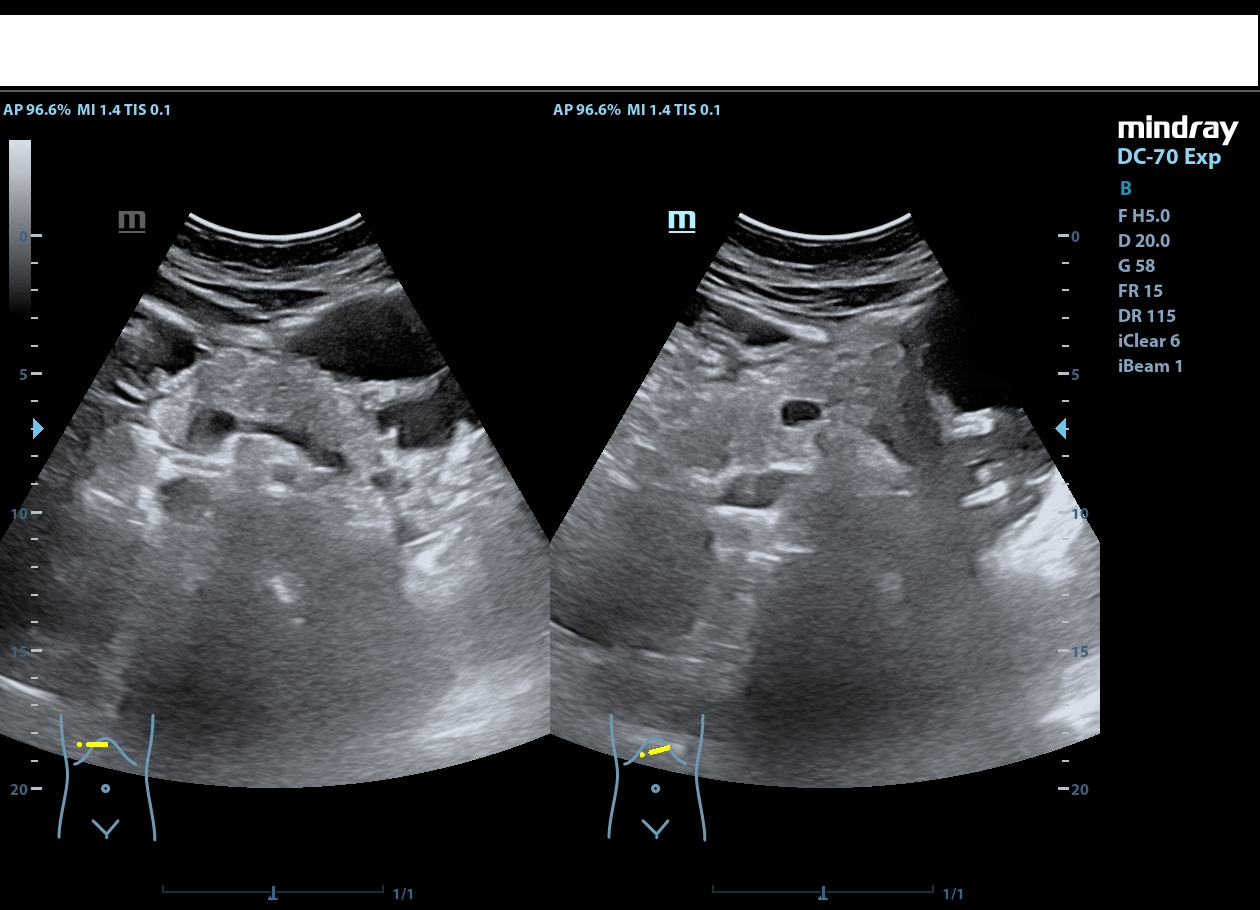

Riñón derecho de ecoestructura conservada, con dilatación pielocalicial grado I. Riñón izquierdo con adelgazamiento cortical y ureterohidronefrosis grado IV, sin poder localizarse el origen de la obstrucción, ausencia de jet ureteral izquierdo. Hallazgos sugestivos de síndrome de la unión pieloureteral.